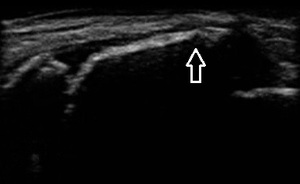

右腓骨遠位端 超音波長軸像 同部3週間後

日常生活では包帯でしっかりと固定し、しばらく体育を休むよう指導しました。3週間後の超音波検査では

骨折部の仮骨形成が進み(右上画像の矢印)、骨癒合している様子が認められたため運動を許可し、

治療を終了いたしました。